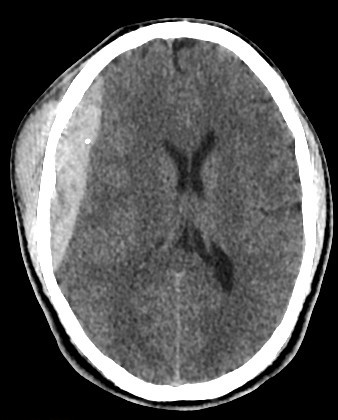

brain CT scan

brain CT scan History